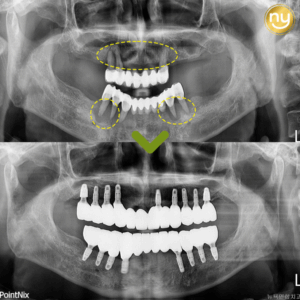

울산안아픈치과 신경치료 후 염증 치아재식술로 해결해요! 안녕하세요. 울산안아픈치과 뉴욕연합치과입니다. 임플란트가 워낙 보편화되고 선호하는 분들이 많아지고 있지만, 자연치아를 살리고자 하는 수요도 급상승하고 있는 추세입니다. 위 환자분은 충치가 많이 진행되어 신경치료한 치아를 사용하고 있었습니다. 하지만, 오랜 기간이 지나 치아 뿌리 끝에 염증이 생겨 발치를 권유받았는데요, 발치를 하더라도 치아 뿌리만 손상 더보기…